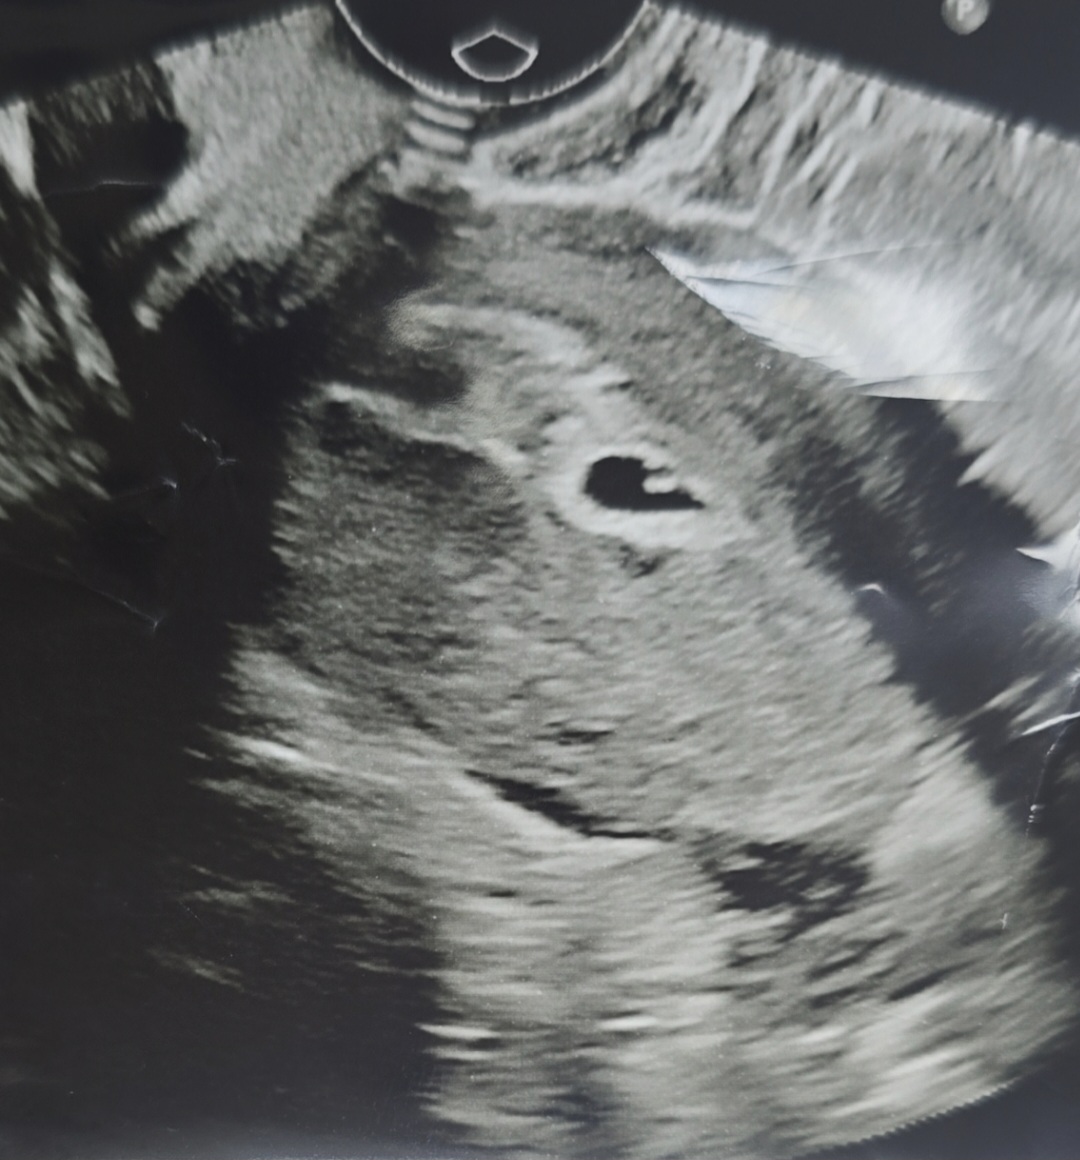

아기집이 찌그러진걸까요? 난황일까요?

전에 하혈을 많이 해서 큰병원 응급실 다녀왔어요. 거기서 찍었던 사진인데 난황으로 보이시나요?ㅠㅠ 아님 아기집이 찌그러져서 그럴까요? 유산 확률 높다는 충격적인 말 듣고 우느라 제대로 물어보지도 못했어요... 지금은 다행히 원래 다니던 병원가서 주사도맞고 질정도 2알씩으로 하다보니 피가 많이 줄었어요. 원래 다니던 병원갔을때 그때 초음파에는 아예 저런 모양이 없어서 물어보니 초기이고 난황은 각도에 따라 안보일수도 있다 하셔서요.. 하혈 멈추려 하는거 같은데 또 다른 불안이 생기네요 ㅠㅠ 들어주셔서 감사합니다.